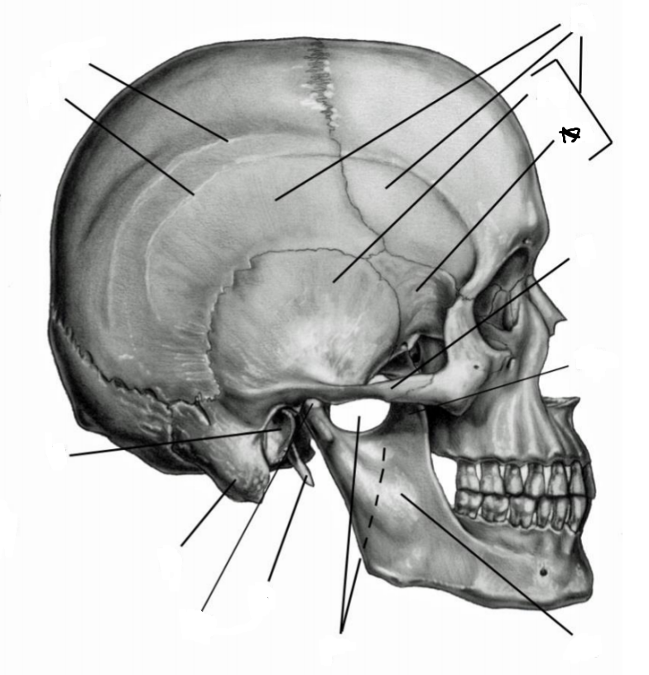

Анатомические особенности: фотографии ямок черепа, височной и подвисочной крылонебной